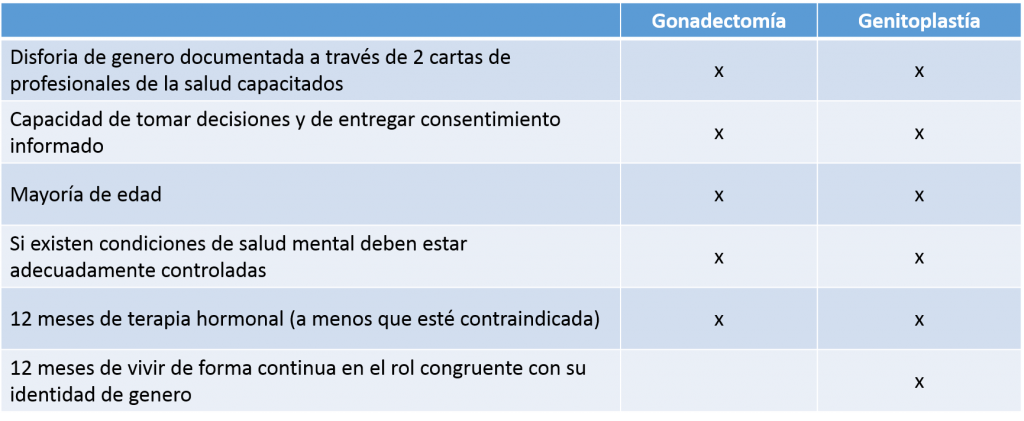

Tabla 1. Criterios WPATH para dos tipos de cirugía genital en personas trans; gonadectomía y genitoplastía. Su descarga es gratuita en este enlace.

Tabla 1. Criterios WPATH para dos tipos de cirugía genital en personas trans; gonadectomía y genitoplastía. Su descarga es gratuita en este enlace.